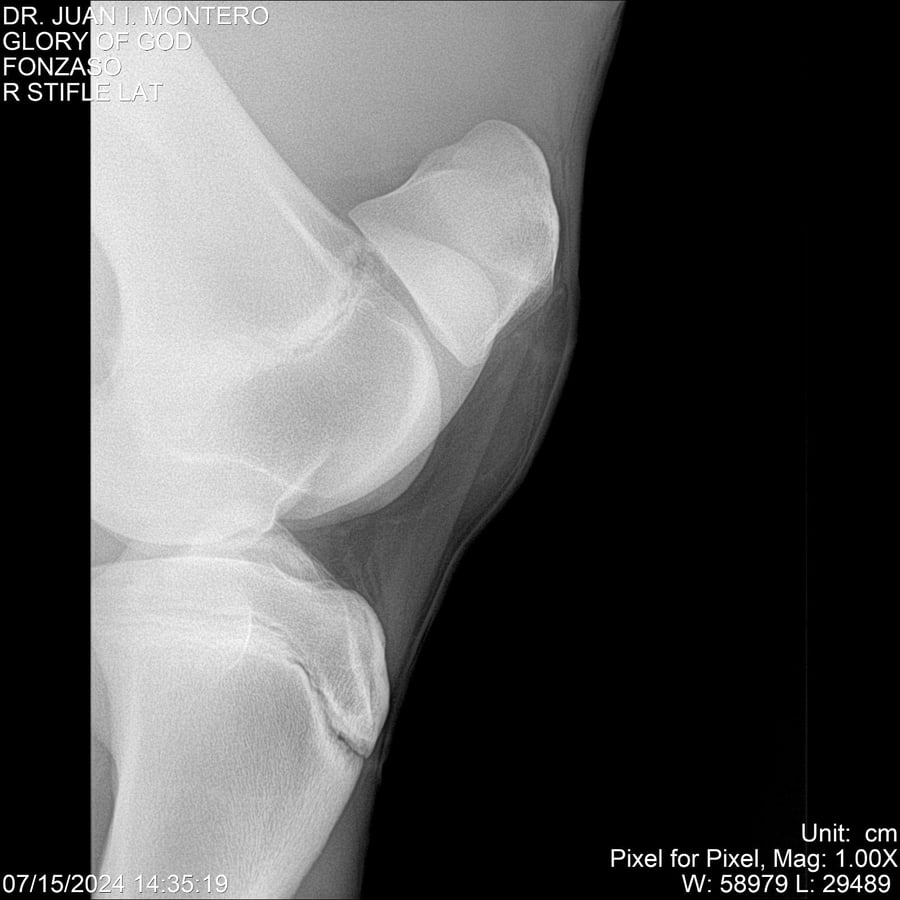

LOTE 10, GLORY OF GOD 🔥 🔥 🔥 Lote Anterior Volver al remate Lote Siguiente Ficha Contacto Montevideo - Ficha del Lote Identificador: #281389 Categoría: Yeguarizos Montevideo - 115 Visualizaciones ClicData Contacto Empresa: Abelenda N. R., Walter Hugo Nombre*: Teléfono* : E-mail* : Mensaje Enviar Registrese gratis Este contenido Exclusivo está disponible sólo para usuarios registrados Ingresar